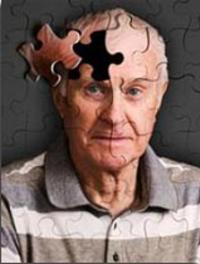

Impact du DES sur le cerveau